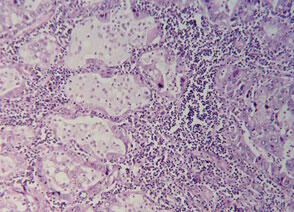

L'activité anticancéreuse de la quercétine a été largement étudiée. En 1989, un rapport a constaté qu'elle inhibait fortement la croissance de cellules de carcinome humain transplantées chez des rats immunocompétents16. Dans différentes expériences in vitro, la quercétine a montré des effets inhibiteurs de croissance de cellules de différents cancers humains : des cellules du côlon, du sein, de l'ovaire, gastro-intestinales ou leucémiques17.

Une étude de phase I a été réalisée sur des patients atteints d'un cancer avancé qui ne répondaient plus à la chimiothérapie. Bien qu'aucun des patients traités ne corresponde à la définition de l'OMS de la réponse d'une tumeur (réponse partielle : 50 % de réduction de la masse de la tumeur pendant plus de 30 jours), deux des onze patients ont eu des résultats positifs. Un patient avec un carcinome hépato-cellulaire a eu une diminution soutenue (150 jours) des alpha-fétoprotéines et des phosphatases alcalines sériques pendant et après une faible dose de quercétine par voie intraveineuse sur un programme de trois semaines. Une patiente avec un cancer de l'ovaire de stade IV qui n'avait pas répondu à six chimiothérapies avec de la cyclophosphamide et de la cisplatine a vu le marqueur de tumeur CA125 chuter de 290 unités/ml à 55 unités/ml après deux injections intraveineuses de quercétine à trois semaines d'intervalle. Le traitement a été poursuivi pendant six mois avec des injections moins fréquentes et l'addition de carboplatine. Les marqueurs de la tumeur ont continué à diminuer. Il n'y a pas d'indication concernant la taille de la tumeur. Il n'y a pas non plus de données concernant les autres patients. L'injection intraveineuse de quercétine a inhibé la tyrosine kinase lymphocytaire chez neuf des onze patients de l'essai19.

Deux études animales ont regardé les propriétés antitumorales de la quercétine. Dans l'une d'elles, des cellules d'ascite tumorales ont été inoculées à des souris qui ont ensuite été traitées par des injections intrapéritonéales de quercétine ou de rutine. La durée de vie des animaux traités quotidiennement avec 40 mg/kg de quercétine a été augmentée de 20 % alors que celle des animaux traités avec 160 mg/kg de rutine était accrue de 50 %.

Une autre étude a regardé l'effet de la quercétine sur des souris portant des tumeurs abdominales provenant d'une lignée humaine de cellules squameuses de carcinome pharyngé. Les souris ont reçu quotidiennement une injection intrapéritonéale de quercétine. Les différentes doses (20, 200, 400 et 800 mg/kg) testées ont inhibé de façon significative la croissance de la tumeur.